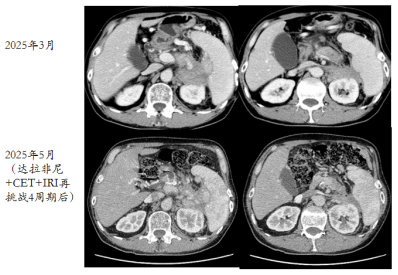

考虑后线治疗有效率低,目前腹痛症状明显,拟行快速缩瘤,与患者及家属商议后,拟再挑战抗BRAF治疗。

2025-03-19开始再挑战达拉非尼+CET+IRI单药治疗。

经过4周期治疗后,患者腹痛及一般情况好转,复查CT评效PR。

image.png

图9 再挑战治疗4周期后复查CT结果